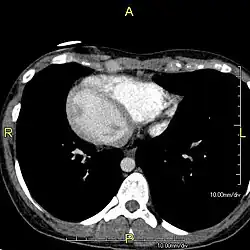

However, in some individuals with PCD, mutations thought to be in the gene coding for the key structural protein left-right dynein (lrd)[4] result in monocilia which do not rotate. There is therefore no flow generated in the node, Shh moves at random within it, and 50% of those affected develop situs inversus, which can occur with or without dextrocardia, where the laterality of the internal organs is the mirror-image of normal. Affected individuals therefore have Kartagener syndrome. This is not the case with some PCD-related genetic mutations: at least 6% of the PCD population have a condition called situs ambiguus or heterotaxy, where organ placement or development is neither typical (situs solitus) nor totally reversed (situs inversus totalis) but is a hybrid of the two.[6] Splenic abnormalities such as polysplenia, asplenia and complex congenital heart defects are more common in individuals with situs ambiguus and PCD, as they are in all individuals with situs ambiguus.[18]

When accompanied by the combination of situs inversus (reversal of the internal organs), chronic sinusitis, and bronchiectasis, it is known as Kartagener syndrome[3] (only 50% of primary ciliary dyskinesia cases include situs inversus).[11]